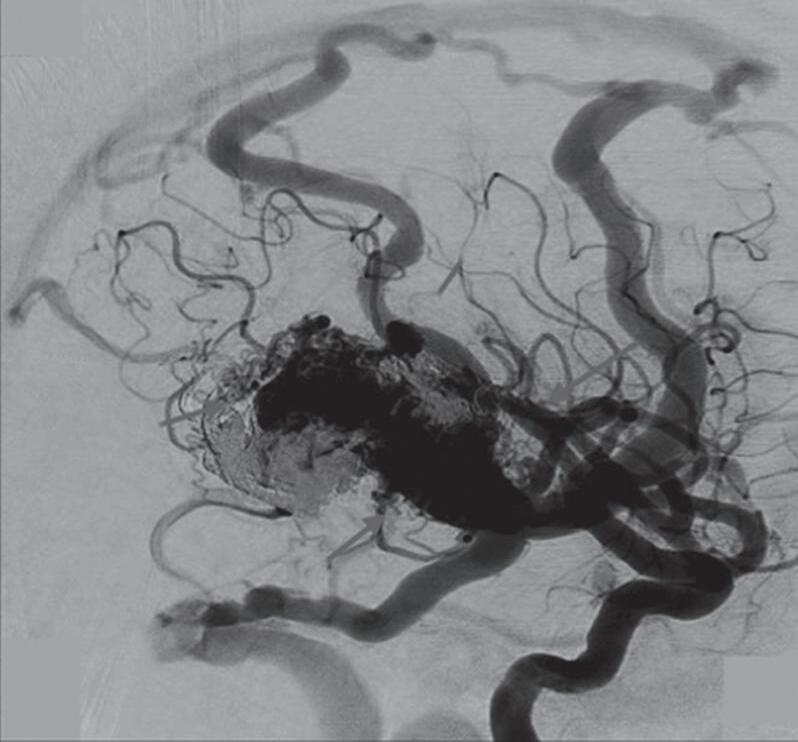

Fig. 1-15. RNM encéfalo T1 (a) sagital sem contraste e (b) axial com contraste demonstrando MAV grau 3, parcialmente embolizada, localizada no giro temporal superior e lobo parietal direito. (c) Arteriografia cerebral em perfil, demonstrando a irrigação pelos ramos da artéria cerebral média e posterior, com drenagem superficial nas veias de Labbé até o seio sigmoide, e o complexo de Trolard no seio sagital superior. O nidus da MAV está demonstrado pelas setas azuis grandes e a drenagem venosa pelas pontas de setas.